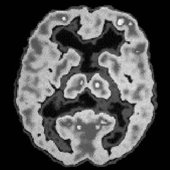

عصب شناسان برای مشاهده اینکه چگونه مغز به درد واکنش نشان می‌دهد و همچنین برای تهیه نقشه سیگنال‌های بخش‌های مختلف بدن از فناوری‌های پیچیده‌ای استفاده می‌کنند.

این شیوه به آنها در اندازه گیری میزان درد ناشی از سیگنال‌های مغزی کمک می‌کند.

دکتر فلاویا مانچینی دانشمند عصب شناختی در دانشگاه کالج لندن و یکی از مجریان تهیه این نقشه، می‌گوید بخش‌های مختلف بدن وقتی دچار درد می‌شوند مناطق خاصی از مغز را روشن می‌کنند.

به گفته وی این امر می‌تواند به پزشکان کمک کند برای نخستین بار بتوانند کمیت درد را به طور عینی مشخص کنند.

در آینده این نقشه، شیوه‌ای برای ردیابی درد در بیماران خواهد بود چراکه یک سیگنال در مغز وجود دارد که نشان دهنده دردی است که فرد در حال تجربه آن است.